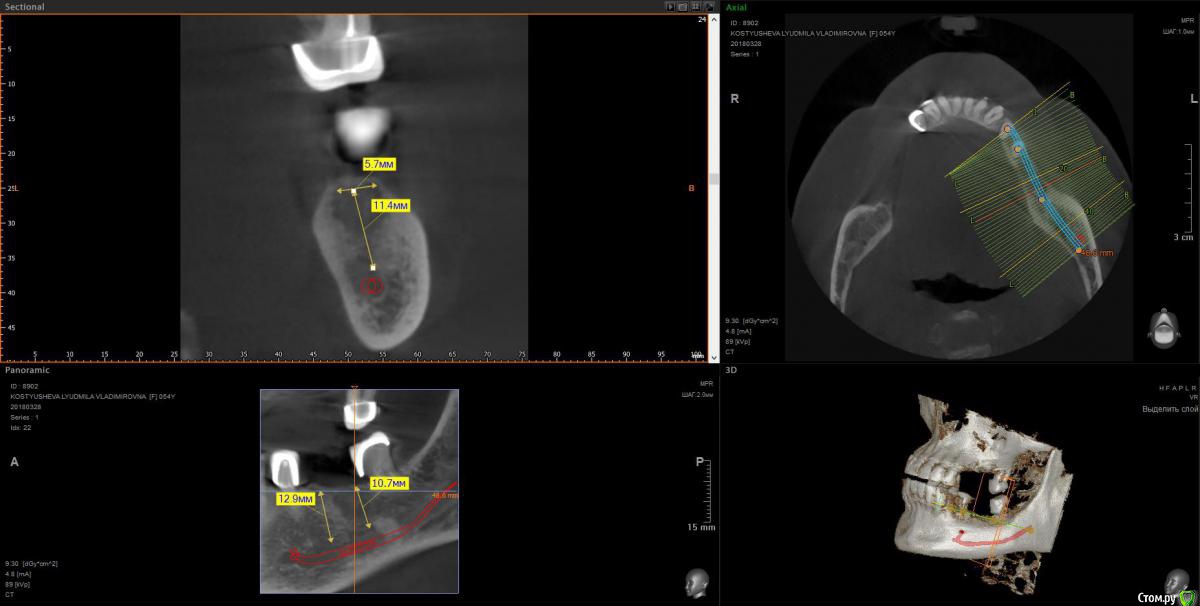

wladdX Опубликовано 11 апреля, 2018 Поделиться Опубликовано 11 апреля, 2018 (изменено) 3-й квадрант Изменено 11 апреля, 2018 пользователем wladdX 1 Ссылка на комментарий

Bier Опубликовано 11 апреля, 2018 Поделиться Опубликовано 11 апреля, 2018 ну да, последний зуб слева я бы удалил. итого 4 имплантата, синуслифтинг на в/челюсти после санации пазухи. 3 Ссылка на комментарий

Irouil Опубликовано 11 апреля, 2018 Поделиться Опубликовано 11 апреля, 2018 (изменено) Про нижнюю челюсть, слева. Левую пазуху В ЛЮБОМ СЛУЧАЕ надо оперировать. P.S. я тут так свободно про тотальное протезирование на верхней челюсти говорю, но у Вас же там передние зубы есть, простите, проглядел. Надо их состояние посмотреть, если в порядке то рассмотрите вариант который Олег Юрьевич описал - по два имплантата со стороны и мосты на них. Да, нужны будут синус лифты, но это высоко предсказуемые операции Изменено 11 апреля, 2018 пользователем Irouil Ссылка на комментарий